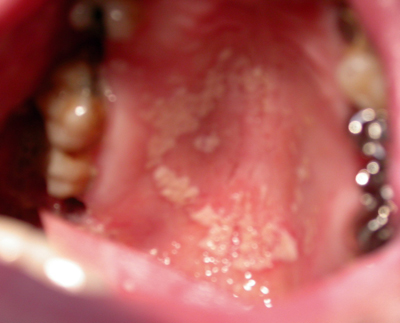

Les infections virales et fongiques (photo n°11)

sont beaucoup plus rares :

La candidose buccale

Elle est liée à des facteurs locaux (irritants, tabac, hyposialie) ou iatrogènes en rapport avec des traitements antibiotiques ou corticoïdes, ou encore généraux (diabète, dénutrition, fièvre, anémie, ra diothérapie).

Le traitement consiste en la remise en état de la cavité buccale, une motivation à l’hygiène, la désinfection prothétique, et un traitement antifongique local de 7 à 14 jours.